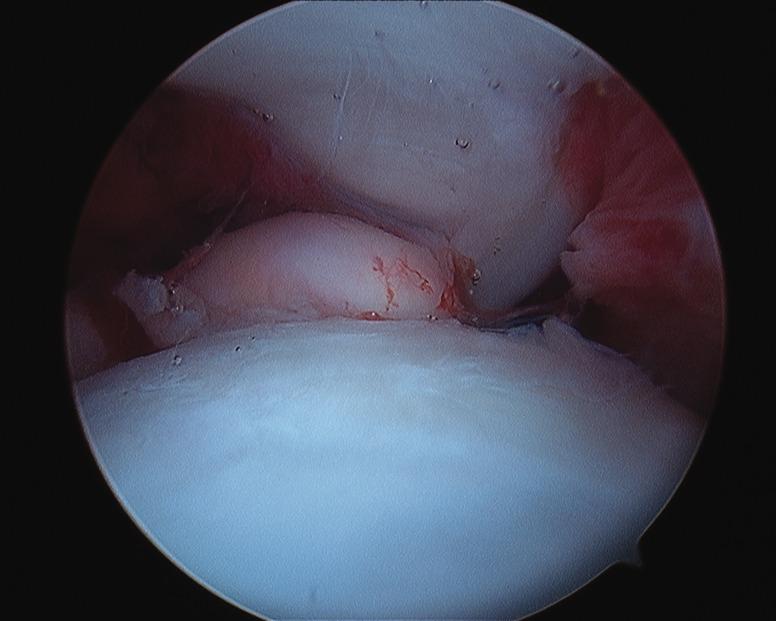

Arthroscopy of the pediatric hip began in 1977 with a publication by Gross. Interest was relatively slow to develop in the 1980s and 1990s. Coupled with the success of hip arthroscopy in the adult, interest heightened in applying the procedure to a variety of pediatric hip disorders, given that the alternative was an open surgical hip dislocation. The success of this initial group of pediatric hip arthroscopist's has further expanded the application of hip arthroscopy as the primary or adjunct procedure for the management of intra-articular problems of the pediatric hip.

小儿髋关节镜检查始于1977年格罗斯发表的一篇文章。在20世纪80年代和90年代,其发展相对缓慢。鉴于成人髋关节镜手术的成功,加上替代方案是开放性髋关节脱位手术,人们对将该手术应用于各种小儿髋关节疾病的兴趣日益浓厚。首批小儿髋关节镜医生取得的成功进一步扩大了髋关节镜检查作为治疗小儿髋关节关节内问题的主要或辅助手术的应用范围。